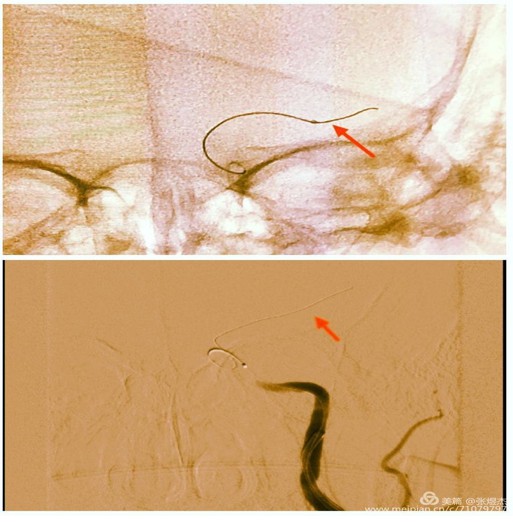

所以既要突破闭塞段,又要保证导丝头端在远端血管腔内,术者的指尖功夫,也就圈内人说的“活”得好啊。大家看下面这两幅图红箭头所指的导丝位置,上幅是顺应血管的走行,下幅只是抬高了10°就已经是穿出血管外了。正所谓差之毫厘、失之千里,等待术者的就只剩下从缺血到出血的冰与火的考验了。